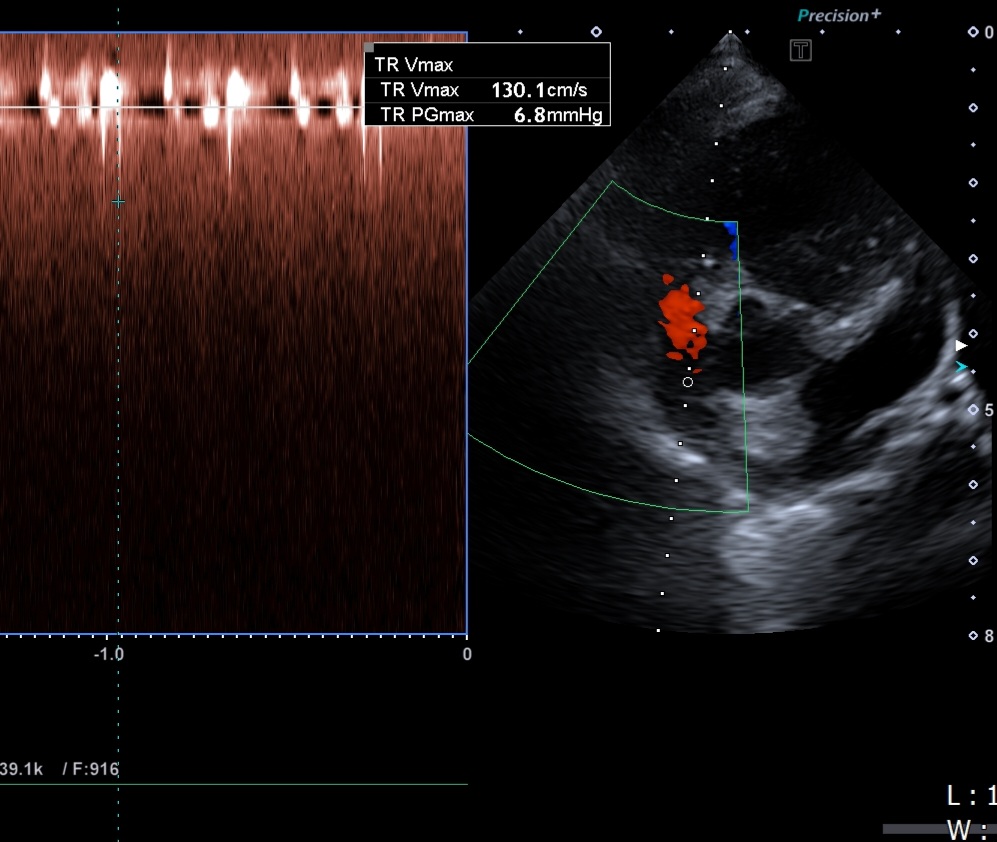

심장병 진단 방법

- 심장초음파(Echo): 판막, 심실 기능 등 직접 확인 가능

※ 정확한 진단은 심장 전문 수의사의 초음파 검사가 필수입니다.